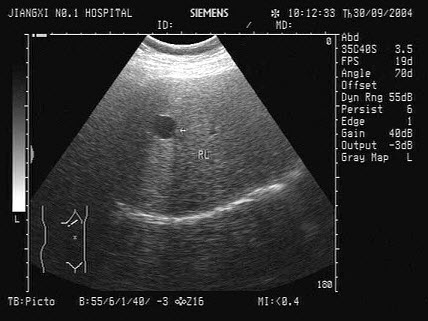

3、单项选择题

男,18岁,外伤1小时就诊。结合超声声像图,诊断为()

A.脾外伤血肿

B.脾淋巴管瘤

C.膈下积液

D.脾皮样囊肿

E.脾血管瘤